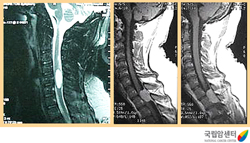

경추부와 흉추부에 발생한 경막외 수막종의 자기공명 영상 촬영 소견

2009.08.21